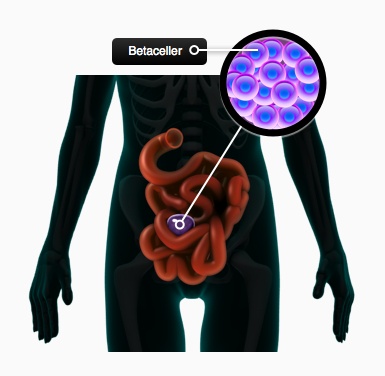

Derfor forsøges det at indkapsle betaceller i en uskadelig men stærk membran, så immunforsvaret ikke kan komme i kontakt med dem. Det er lykkedes at indkapsle betaceller i en såkaldt PEG-membran, og at transplantere cellerne til den væske, der ligger mellem tarmene. Denne væske er i forbindelse med blodbanen, og betacellerne kan derfor regulere koncentrationen af glukose i blodet. Der er dog flere problemer forskerne skal klare. Det kan ske, at overfladen af membranen bliver dækket med immunceller eller bindevævsceller. De kan ikke komme til betacellerne, men blokerer for at stoffer kan passere membranen. Vha. nanoteknologi forsøger forskerne derfor at lave en overflade på membranen, så andre celler ikke sætter sig fast. Behandlingen virker ret godt på mus, men der er store problemer med at overføre teknikken til mennesker. Selv om immunforsvaret i mennesker og mus ligner hinanden meget, er der forskelle. Behandlingen forventes at kunne bruges sammen med betaceller lavet fra stamceller, hvis det lykkes at få den til at fungere i mennesker.

Figur 35. Betaceller indkapsles i en nanomembran og placeres mellem tarmene. Da væsken mellem tarmene er i forbindelse med blodbanen, kan betacellerne regulerer blodsukkeret herfra.